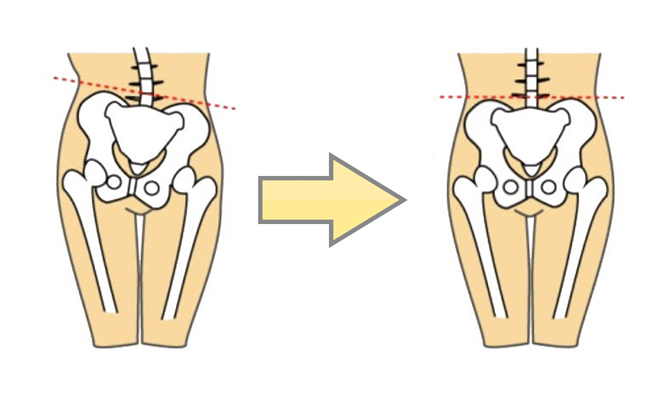

骨盤の傾き

なぜ?この姿勢が「妊娠できにくい姿勢」なのかを説明いたします。

骨盤が後傾して、背中が丸くなることで、足を組みやすくなったり、正座を崩す横座り姿勢になることで、

骨盤が左右に傾き、内臓の圧迫も加わり、子宮、卵巣、卵管が傾き捻じれることで、生殖機能が低下してしまい、更に妊娠できにくくなってしまいます。

現代人の多くが、妊娠力が低い状態「妊娠できにくい姿勢」になっています。

病院では、妊娠力がとても低くなっている状態を改善せず、「受精」「着床」の確立を高めることしかできません。

大切なのは、

「低くなっている妊娠力を高めてあげること」なのです。